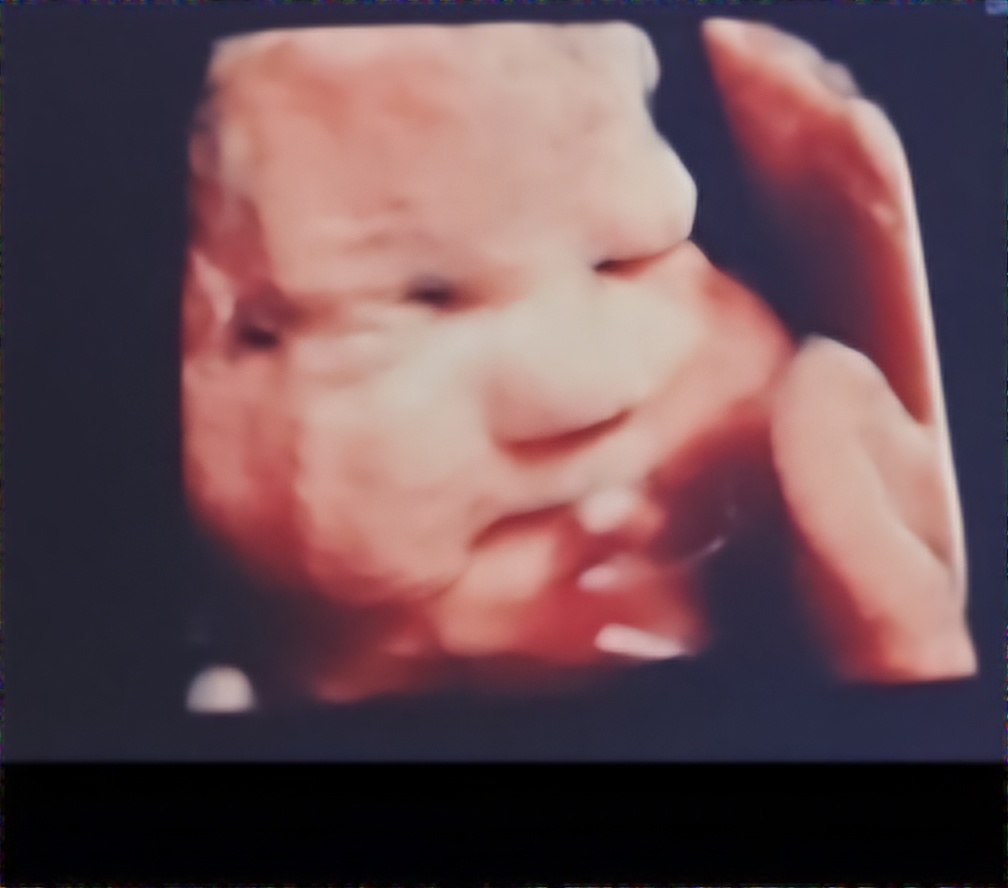

CULLMAN, Ala. – Cullman resident Holliann Letson was enjoying a typical pregnancy with her second daughter, Evelyn. At her 18-week anatomy scan – the scan often referred to as the “gender scan,” as most babies’ genders can be determined at this stage of pregnancy – Letson was hit with some devastating news. Her daughter had an anomaly near her heart.

“The doctor advised me to forget all about the congenital hernia. Evelyn was misdiagnosed,” Letson said. Evelyn’s new diagnosis was one of congenital pulmonary airway malformation, a “mass of abnormal lung tissue, which may be filled with fluid or other material.” (Texas Children’s Hospital). “This prognosis is so much better, but no less immediately dangerous.”

The same day, Letson underwent urgent surgery to place a shunt in her baby’s chest cavity and relieve pressure on the heart. She was told that without the surgery and shunt placement, the fluid would slowly build and likely cause Evelyn to go into cardiac arrest within weeks.

Letson smiled and said, “I had the procedure, and the next day the fluid in her chest had decreased significantly.”

Now, more than a month after that unexpected procedure, Evelyn’s chances of survival have soared from 30% to 70%. Not quite out of the woods, Letson will travel again to Houston on the morning of Tuesday, July 23, for the third time to make delivery plans and discuss outcomes and possible treatments for Evelyn at birth.